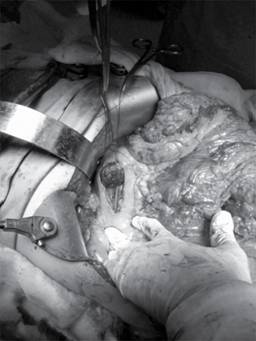

Previo al corte del páncreas debe asegurarse el margen oncológico macroscópico, se colocan puntos de referencia en los extremos superiores e inferiores con sutura no absorbible (polipropileno calibre 000) en cuatro sitios, los cuales son determinados por límite del margen quirúrgico, dos para la pieza quirúrgica (superior e inferior) y dos para el muñón pancreático (superior e inferior). Se procede al corte del páncreas entre estos postes de sutura con la finalidad de que sean hemostáticos y para tracción. Se completa la resección de la pieza quirúrgica y una vez concluida la pancreatoduodenectomía tiene que realizarse una disección del muñón pancreático residual utilizando los hilos de tracción previamente colocados, movilizarlo sin comprometer la vasculatura. Se mide el muñón pancreático y se corrobora que el conducto esté permeable. La finalidad de la movilización es tener suficiente tejido pancreático que pase a través de la pared gástrica posterior y así poder colocar puntos de fijación con material no absorbible (Figura 1).

Figura 1: En la imagen se observa el muñón pancreático remanente traccionado por las suturas previa disección y movilización para poder realizar la anastomosis a través de la pared posterior del estómago.